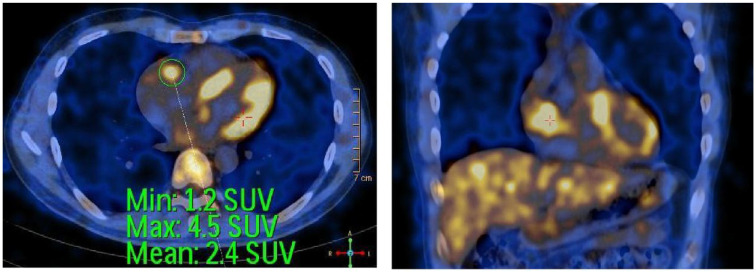

Heart tumors are sporadic. Secondary heart tumors are 30 times more common than primary ones. Depending on the location and origin of the tumor, clinical pictures vary from asymptomatic to severe manifestations such as arrhythmia, heart failure, pericardial effusion, and cardiogenic shock. We report hereby a rare case who presented with faint clinical symptoms, rapidly progressing to right heart failure within a month. Echocardiography and computed tomography of the chest revealed a tumor in the right heart chamber of 72.0 × 43.0 mm, in addition to large mediastinal lymph and left supraclavicular lymph nodes, cardiogenic shock appeared 4 days after admission. Through examination, it was suspected that this was a cardiac lymphoma. The patient was treated with 2 mg methylprednisolone per kg body weight. Symptoms of cardiogenic shock improved significantly and disappeared after 6 hours of treatment. After supraclavicular lymph node biopsy and immunohistochemistry, the final result was diagnosed as diffuse large B-cell non-Hodgkin lymphoma with large lymphoma in the right heart. The patient received chemotherapy with the R-CHOP regimen (Rituximab, Cyclophosphamide, Doxorubicin, Vincristine, and Prednisolone). Re-examination before the 5th chemotherapy cycle showed no signs of right heart failure, normal self-activity, and no dyspnea on exertion, and the tumor size in the heart on the echocardiogram was 23.8 × 19.1 mm. The report shows that a large right heart tumor with a clinical picture of cardiogenic shock in a patient with diffuse large B-cell non-Hodgkin's lymphoma was well-responded to initial treatment with methylprednisolone at a dose of 2 mg/kg body weight and R-CHOP chemotherapy.